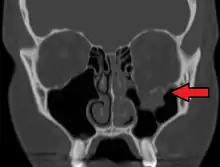

Radiography, imaging of tissues using X-rays, is used to rule out facial fractures.[2] Angiography (X-rays taken of the inside of blood vessels) can be used to locate the source of bleeding.[10] However the complex bones and tissues of the face can make it difficult to interpret plain radiographs; CT scanning is better for detecting fractures and examining soft tissues, and is often needed to determine whether surgery is necessary, but it is more expensive and difficult to obtain.[4] CT scanning is usually considered to be more definitive and better at detecting facial injuries than X-ray.[3] CT scanning is especially likely to be used in people with multiple injuries who need CT scans to assess for other injuries anyway.[11]